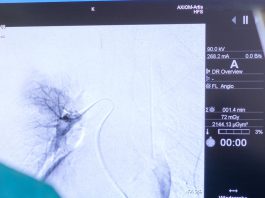

Παθήσεις χοληφόρων – PTC

Tι είναι η PTC;

Είναι η διαδερμική απεικόνιση και παροχέτευση του αποφραγμένου χοληφόρου συστήματος.